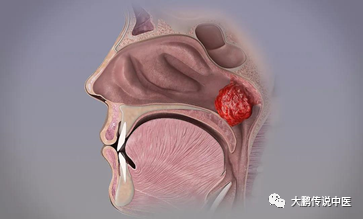

所以,详细的症状评估和检查是第一位的,如果孩子出现鼻塞,张口呼吸,打鼾、睡眠影响等问题,可以做检查。目前腺样体检查法包括间接鼻咽部触诊、鼻咽镜检查、鼻咽侧位X片。鼻内窥镜检查能够直接反映腺样体的大小、颜色、形态、是否压迫咽鼓管咽口及堵塞后鼻孔的面积,此检查安全性及诊断准确性较高。鼻咽部侧位X线片检查及鼻咽部CT检查,能够测量鼻咽气道阻塞程度,观察邻近骨质,易于鉴别诊断。

简单说,腺样体肥大就是腺样体出现了肿大,并且出现影响生活的症状。腺样体肥大可由感染或非感染因素引起。腺样体是免疫器官,学龄前儿童是免疫器官增殖期,或多或少的都有部分增生,加上其本身也会被病原侵袭感染,而感染后,就会出现发炎等问题,就像扁桃体炎一样。

腺样体肥大不是一下就堵塞了,如果仅有一次急性感染,那么腺样体肿大通过治疗后,就逐渐恢复了,没啥大问题;但是如果长期反复的感染,那腺样体就会不停的受到刺激,出现过度的、持久的增生,就会阻塞鼻咽处,出现鼻塞、张嘴呼吸、打鼾等症状,就称为腺样体肥大了。